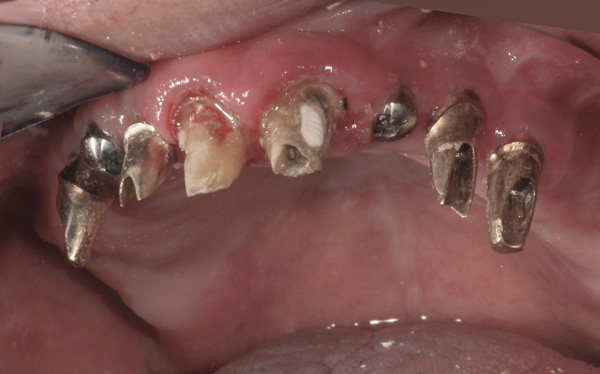

Background: This patient had a failing maxillary dentition and refused to wear a removable prosthesis. A staged approach was employed to retain some of his natural tooth abutments, and recession was noticed at the time of the impression for the second group of implants. Figure 1 shows the patient following insertion of the first set of implant custom abutments; the adjacent natural teeth are still present to support the provisional bridge. Seven months later, as shown in Figure 2, those first-stage custom abutments exhibited evidence of 1 mm to 3 mm of recession.

Figure 1  Patient following insertion of first set of implant custom abutments.

Figure 1

Figure 2 After 7 months, the first-stage custom abutments exhibited evidence of 1 mm to 3 mm of recession.

Figure 2